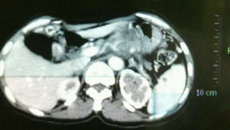

V\:*{behavior:url(#default#VML);}O\:*{behavior:url(#default#VML);}W\:*{behavior:url(#default#VML);} 春节刚过,喜庆气氛尚未散去,来自广西平南的赵大妈却无法享受节日的欢乐。因为手术的原因,她已经在我院肝胆肠外科的病床上躺了两个星期了,现在赵大妈急切地期望能够早点康复,结束那不堪忍受的胃痛。 “今年5月份的时候胃疼得受不了,走不了路,干不了活,连觉都睡不着。除了粥什么都吃不下,到现在已经吃了半...03.012013